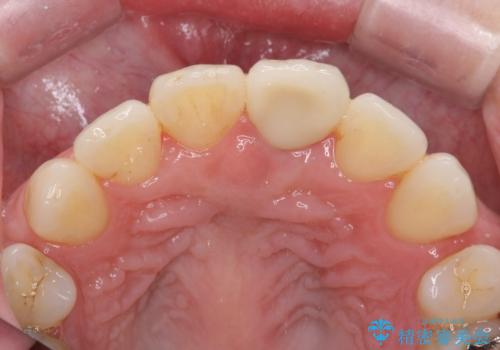

- 神経の治療をしたまま放置していた歯が、変色してきたので改善したい。と前歯の審美性の改善を求めて来院されました。

根管治療後の歯には部分的な修復処置が為され、変色が進行している状態でした。

ジルコニアクラウンを用いて、自然な色調となるよう治療を計画します。

根管治療は行わず、仮歯・ジルコニアクラウンのみの処置を行い自然な歯に仕上げることができました。